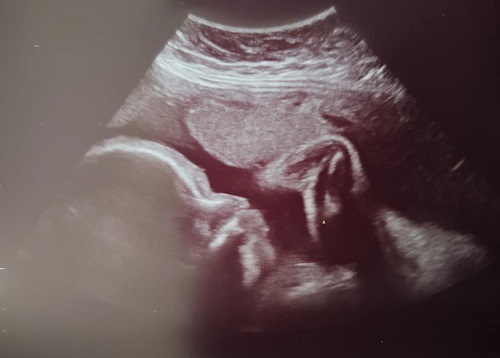

We were able to see his face pretty good at one point. This is where I wish the doctor had a 3-D machine. I can only imagine how amazing he looks in 3-D.

It was pretty awesome to get him looking right at us.

The tech then snapped a profile picture, in which you can see his foot up in the air, and finished with the measurements. He is about 4 pounds right now. He will gain 1/2 pound every week from here on out. They are guessing he will be about 8 pounds 8 oz when he is born.